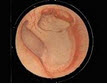

慢性化脓性中耳炎,鼓膜穿孔位于前后皱襞及锤骨短突之上者,如图所示,称为()

A、中央性穿孔

B、紧张部穿孔

C、边缘性穿孔

D、松弛部穿孔

E、上述都不是

D